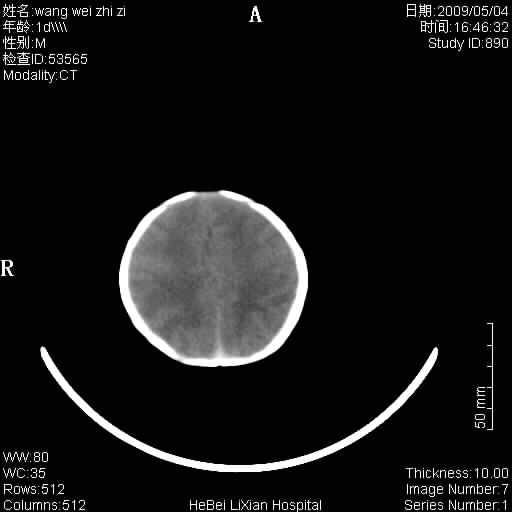

患者,男,1天,上肢抽动数次伴气促.有急产史.可以诊断珠网膜下腔出血吗?

局部5毫米薄层扫描

缺血缺氧性脑病,蛛网膜下腔出血。

此例符合缺血缺氧性脑病并蛛网膜下腔出血.